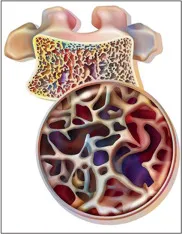

Este vídeo apresenta, de forma didática e baseada em evidências, os principais achados da tese de doutorado sobre amiloidose renal, com foco em proteômica glomerular e ativação do complemento. São discutidos aspectos diagnósticos, implicações fisiopatológicas e correlações clínico-patológicas relevantes para a prática do nefrologista. O conteúdo sintetiza dados inéditos de matriz extracelular glomerular e diferencia perfis entre subtipos de amiloidose. Trata-se de um material aprofundado e acessível, ideal para atualização de especialistas na área.